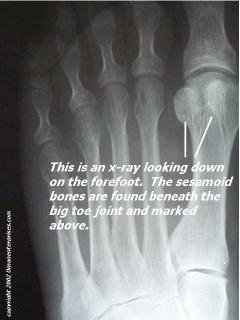

Most bones in the human body are connected to each other at joints. But there are a few bones that are not connected to any other bone. Instead, they are connected only to tendons or are embedded in muscle. These are the sesamoids. The kneecap (patella) is the largest sesamoid. Two other very small sesamoids (about the size of a kernel of corn) are found in the underside of the forefoot near the great toe, one on the outer side of the foot (lateral) and the other closer to the middle of the foot (Medial). these sesamoids are embedded in the flexor hallucis brevis tendon, one of several tendons that exert pressure from the big toe against the ground and help initiate the act of walking.It is not uncommon for people to have more then two sesamoids on the great toe as well. this condition is called Biparte sesamoids and can easily be misdiagnosed as a fracture of one of the medial or lateral sesamoids, when infact it is a third sesamoid in its own right. Because the edges of a bipartite medial sesamoid are generally smooth, and the edges of a fractured sesamoid are generally jagged, an X-ray is useful in making an appropriate diagnosis. Your physician may also request X-rays of the other foot to compare the bone structure.

typical sesamoid x-ray |